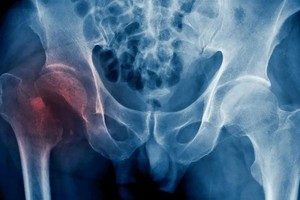

Las fracturas más comunes ocurren en la muñeca, la cadera y la columna vertebral, zonas que con el tiempo y la pérdida de masa ósea se debilitan al punto de que actividades cotidianas o caídas menores pueden desencadenar una fractura.